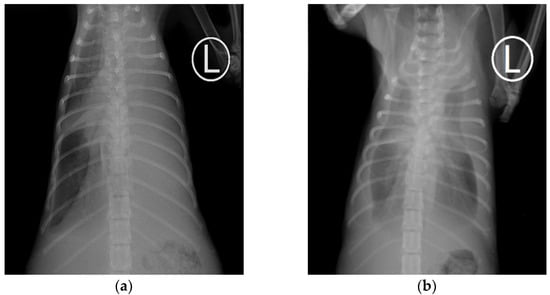

3.4. Radiographic Findings

| Radiographic Findings | Number of Cases (n) | Percentage (%) |

|---|---|---|

| Pleural effusion | 28 | 100 |

| Unilateral | 9 | 32.1 |

| Bilateral | 19 | 67.9 |

| Lung consolidation | 21 | 75.0 |